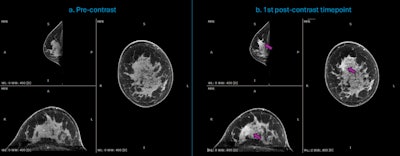

Dedicated breast CT acquisitions of a 44-year-old woman with newly diagnosed invasive ductal carcinoma (IDC) of high aggressiveness (grade 3) in the right breast. (a.) Multiplanar reconstruction of the precontrast acquisition (t = 0 seconds); (b.) Multiplanar reconstruction of the first acquired postcontrast timepoint (t = 90 seconds), indicating the enhancing malignant lesion (purple arrow), in a case with strong background parenchymal enhancement (BPE). Courtesy of Dr. Ritse Mann, NKI, Netherlands Cancer Institute.

The mean contrast-enhanced signal intensity of the lesions (μSLE = 123.8 Hounsfield units [HU]) was highest at the first postcontrast time point (90 seconds), with an average increase of 59.6 HU compared to the baseline. No relevant washout was observed over the following time points (p > 0.05), but later time points showed increased BPE, achieving the highest mean signal intensity (μSBPE = 108.3 HU) at the fourth postcontrast time point (t = 150 seconds). The average CNR across the 30 cases showed the highest values (CNR = 2.23) at the first time point (t = 90 seconds) and (CNR = 1.62) at the first subtracted image.

“Contrast enhancement and image quality metrics proved that the optimal postcontrast time point is 90 seconds,” Tsarouchi stated. “As BPE increases in later time points, scanning earlier may improve lesion detection.”